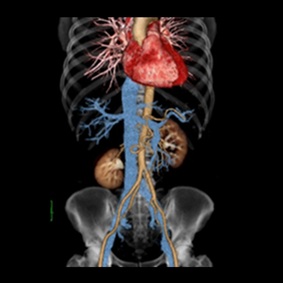

CT検査とは多方向からX線を照射し、身体の断面を撮影する検査です。

また、撮影した画像を重ね合わせることにより立体画像を構築し、より細かい診断ができます。

フィリップス社製のingenuity core(64列)というマルチスライスCT装置を導入しています。

この装置は1回転の間に64画像(スライス)を撮影することが出来るため、短時間で広範囲の撮影を行うことができます。

また、心臓のような動きのある臓器でも高精細な画像を得ることができます。